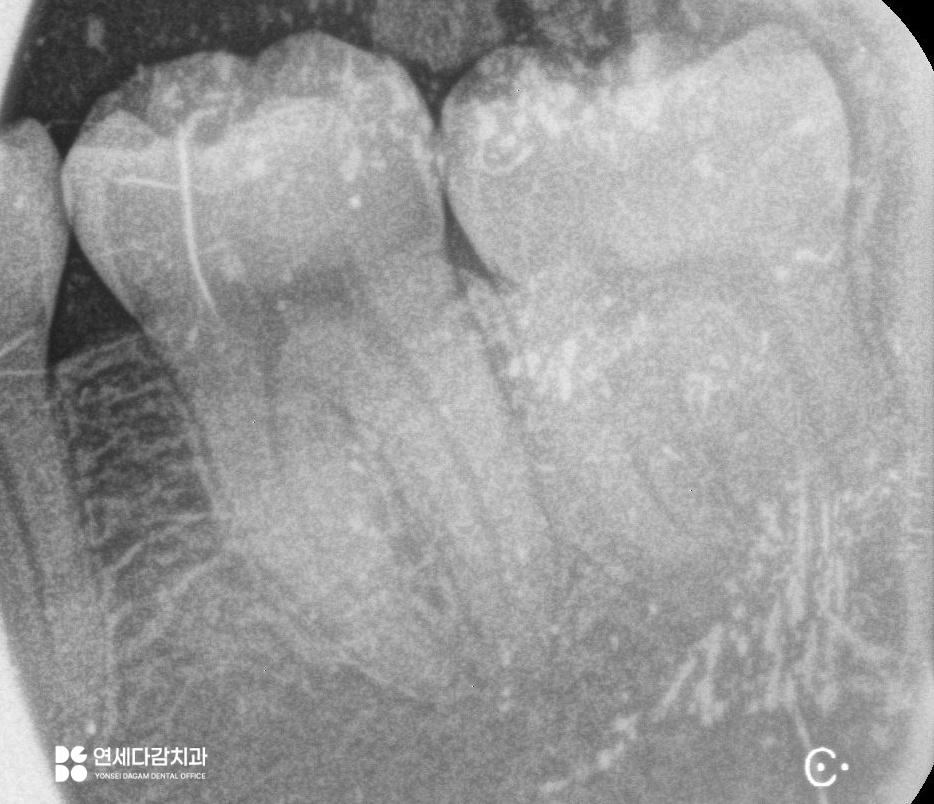

이는 2차원적인 엑스레이와는 다르게

입체적으로 치근단과 신경관의 관계를

시각화여 보여주는 장비입니다.

주행 경로를 정확히 파악할 수 있으며,

치아 뿌리의 각도와 방향까지 정확히 보여주어

발치 시 어떻게 분리해야 될지

어떤 방식으로 접근해야 되는지에 대한

섬세한 계획을 세울 수 있습니다.

해당 케이스는 신경관이 치근 끝에 닿아 있어

최소한의 자극으로 진행해야 됩니다.

특히 원심 부위는 잇몸 속에 묻혀 있으므로

절개 후 뼈를 정리하는 과정이 필요합니다.